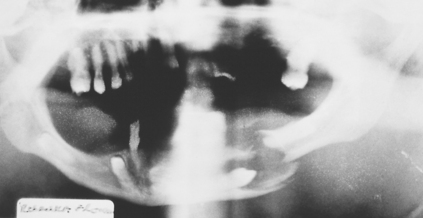

Many cysts show a predilection for specific areas. For example, 75% of odontogenic keratocysts present at the mandibular angle (Fig. 9.3) whilst 88% of glandular odontogenic cysts occur at the anterior mandible (Cawson et al. 2001). Some cysts are completely site-specific such as the nasopalatine duct cyst, which arises from tissues within the incisive canal, and the paradental cyst, which is associated with impacted lower third molars. Also of note is the group of cysts that present in the gingival area including the inflammatory lateral periodontal cyst (a variant of a radicular cyst), the true lateral periodontal cyst, the peripheral odontogenic keratocyst and gingival cyst of adults. These classically present coronal to the apices and in-between teeth in the premolar areas.

image

Fig. 9.3 An odontogenic keratocyst at the angle of the mandible.

Cysts that develop by fluid accumulation and consequent hydrostatic pressure, e.g. inflammatory and dentigerous cysts, will develop spherically and so expand through cortical bone relatively early. In contrast, odontogenic keratocysts grow by cellular proliferation. Expansion tends be to a late feature, with the keratocyst preferentially expanding within the cancellous bone, leading to a greater anteroposterior dimension on radiographic examination.

Lobulation

Where a radiolucency displays lobulation it is strongly suggestive of the keratocyst (Fig. 9.3), which has a pattern of cyst growth with ‘invasion’ of lining epithelium through the cancellous bone space leaving behind isthmi of bone.